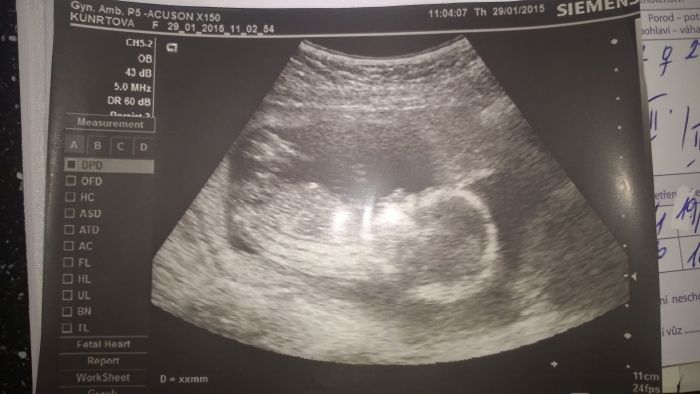

Ach jo. Doufám, že Nicolce nějak pomůže. Jinak já teda taky nabírám jak blázen. Už se nevejdu ani do těhu oblečení a vše mě škrtí na podbřišku, tak budu muset asi něco vymyslet. A zapomněla jsem vám dát fotku miminka. Snad se příště ukáže. Kajdi, moc na tebe myslím a Ell, určitě po takové romatice to musí také vyjít :)